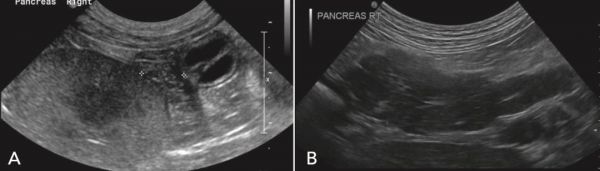

图1.胰腺炎的超声图像显示:( A)慢性胰腺炎犬胰腺的不均匀回声;( B)急性胰腺炎犬胰腺显著增大,胰腺内出现低回声区,胰周脂肪附近出现高回声。